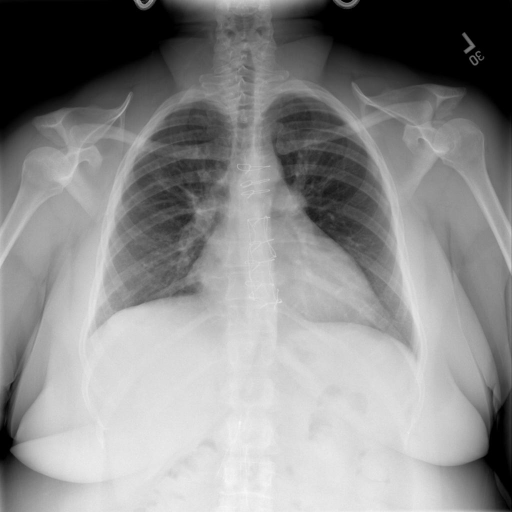

|X光影像|诊疗报告(医生)|XrayGLM|

||根据X射线图像,心脏大小正常,肺部看起来很清晰。已经排除了肺炎、积液、水肿、气胸、腺病、结节或肿块的存在。该发现表明一切正常。换句话说,总体印象是胸部正常。|X光片显示,心脏大小正常。肺部没有气胸或胸腔积液的证据。骨骼结构看起来没有任何异常。总的来说,X光片表明没有发现急性心肺疾病的迹象。|